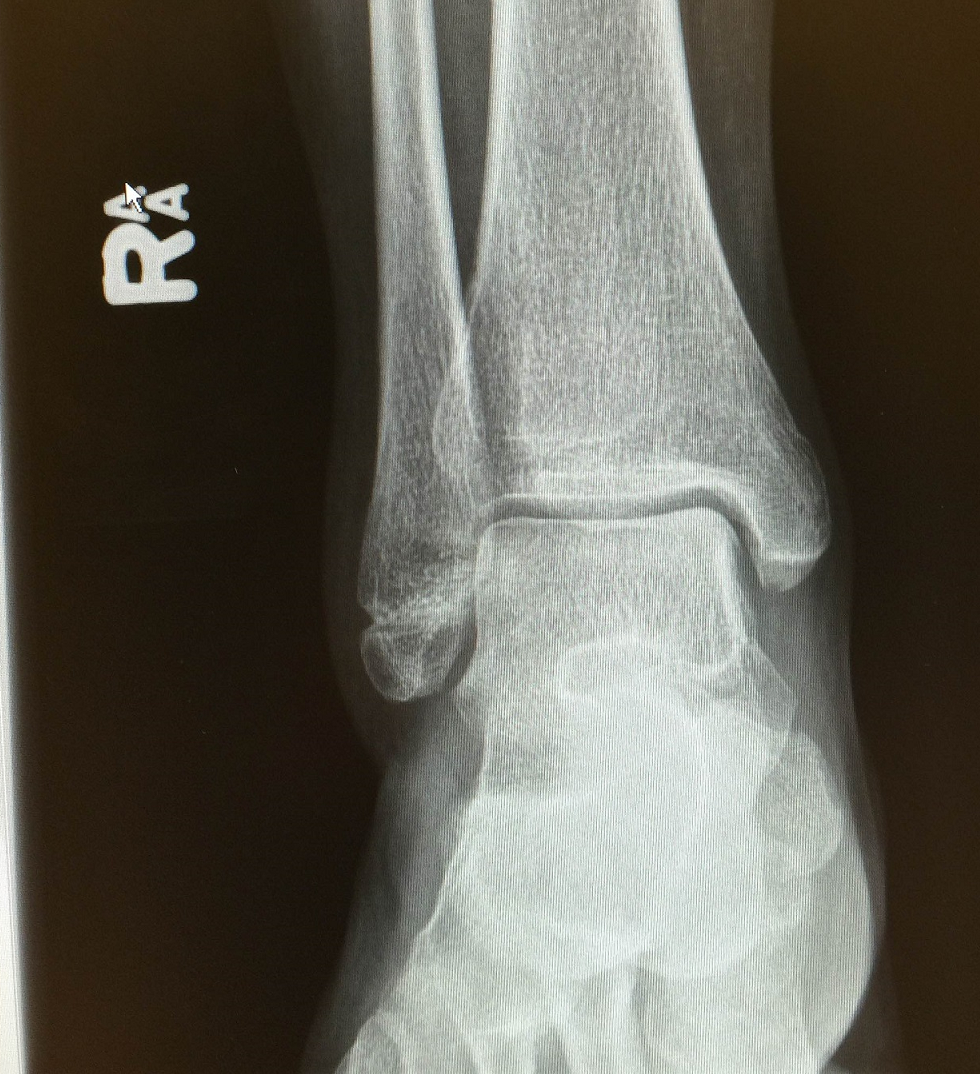

左脚踝骨折,骨裂,手术上钢板

医生您好,今年九月中旬摔倒,把右脚踝的腓骨末端给弄骨裂了,骨_骨折